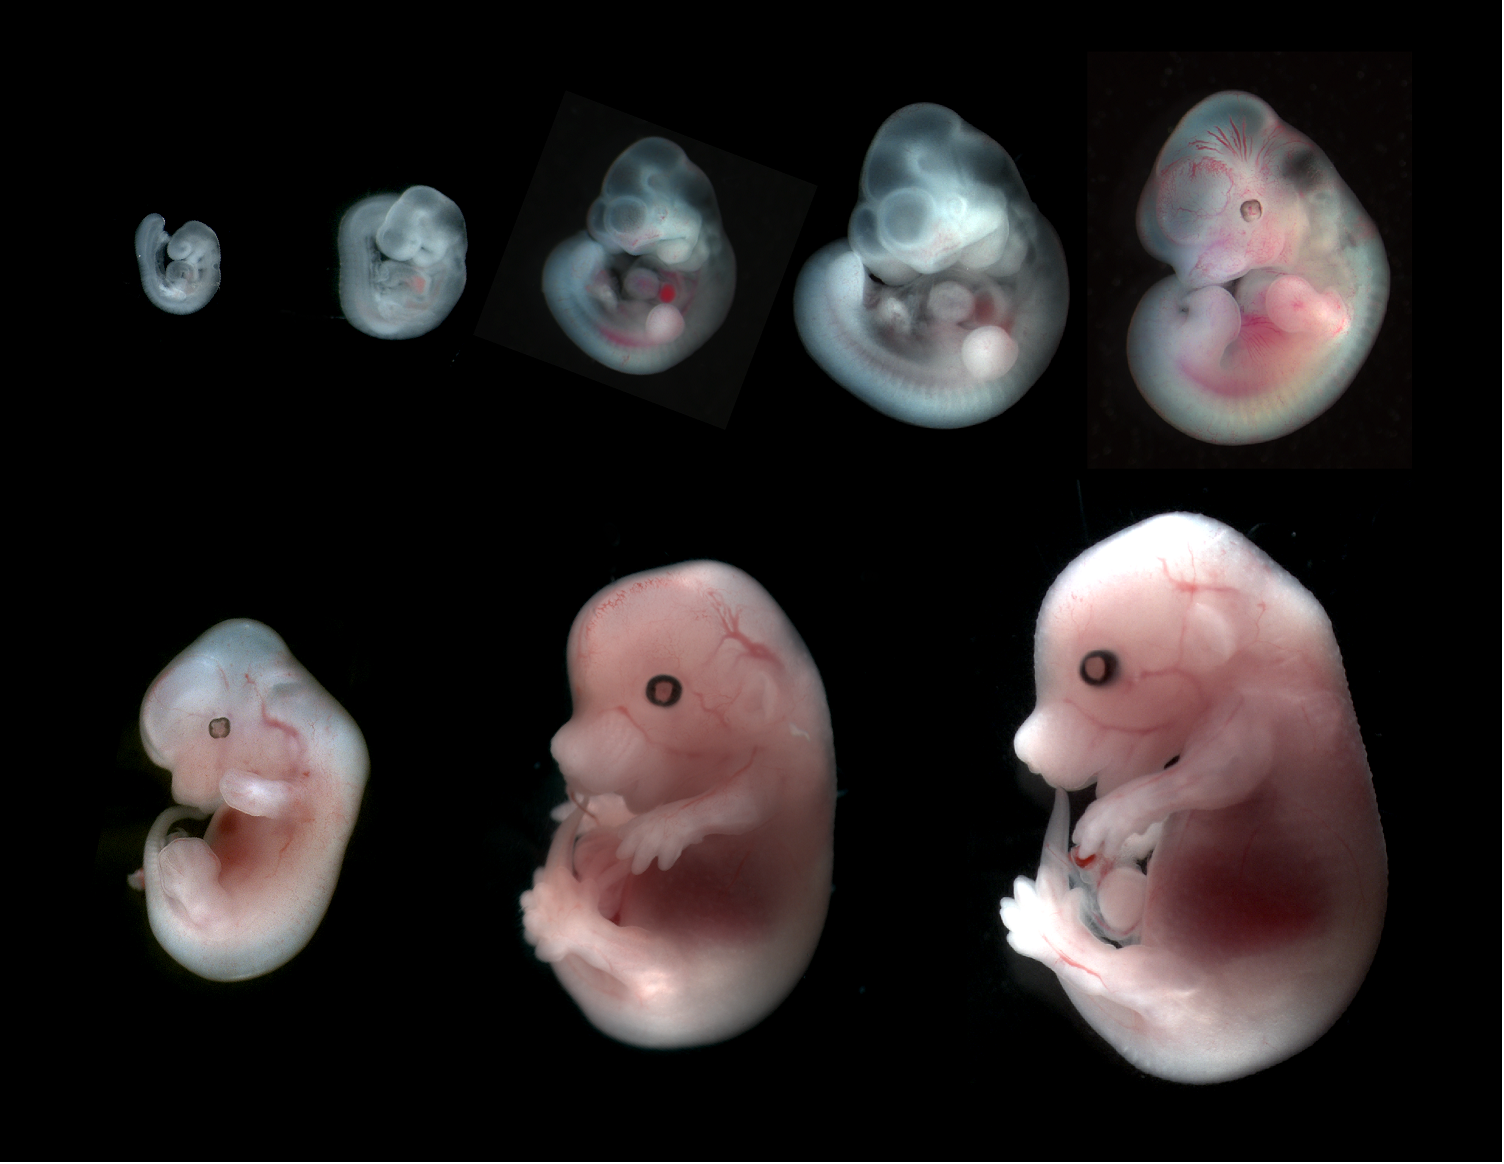

Эмбриональный период: Развитие эмбриона от зачатия до рождения